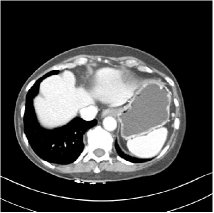

Fig. 3: Three examples (from top to bottom) of the reconstructed testing images using Momentum-Net with SimpleCNN (the second column), with SimpleCNN-RSN (the third column), and with Dn-RSN (the fourth column). The compared WavResNet denoised images are shown in the first column, and the reference images are in the fifth column. See their FBP images in Fig. 4.

Fig. 4: FBP images of test examples.

Fig. 2 shows that the proposed Momentum-Net with SimpleCNN decreases RMSE dramatically in the first 30 layers, and tends to converge in 50 layers. The Momentum-Net reduces the mean RMSE value by 4.5 HU and gives smaller standard deviations in RMSE, compared to WavResNet, as reported in Table 1. This implies that the proposed Momentum-Net with SimpleCNN can improve both the accuracy and stability of low-dose CT image reconstruction than a state-of-the-art image denoising deep NN, WavResNet. The proposed Momentum-Net with SimpleCNN better removes noise and streak artifacts than WavResNet. It also provides clearer reconstructions of some details; see, in Fig. 3, the boundaries shown in the zoomed region at the top-right corner in the first example, the arrow pointed structures in zoomed areas of the second example, and the arrow pointed tissues in the left zoomed region in the third example.

We show the reconstructed examples by Momentum-Net with SimpleCNN-RSN and Dn-RSN in the third and fourth columns of Fig. 3 respectively. Comparing the first three and the last columns in Fig. 3, we observe that Momentum-Net with SimpleCNN-RSN provides generally noisier reconstructions than WavResNet and Momentum-Net with SimpleCNN. However, Momentum-Net with SimpleCNN-RSN sometimes can provide clearer details than WavResNet. For example, in the right zoomed box of the second example, Momentum-Net with SimpleCNN-RSN shows better reconstruction quality for the arrow pointed structures than WavResNet, and in the left zoomed box in the third row, the former gives clearer small tissues marked by red arrows than the latter. Table 1 reports that Momentum-Net with SimpleCNN-RSN is approximately 2.9 RMSE (HU) higher than WavResNet, while it has smaller standard deviations. This implies that Momentum-Net with SimpleCNN-RSN is more stable than WavResNet, although it may not provide better image qualities. Momentum-Net with Dn-RSN, however, provides the worst visual and numerical results among the compared four methods in this paper.